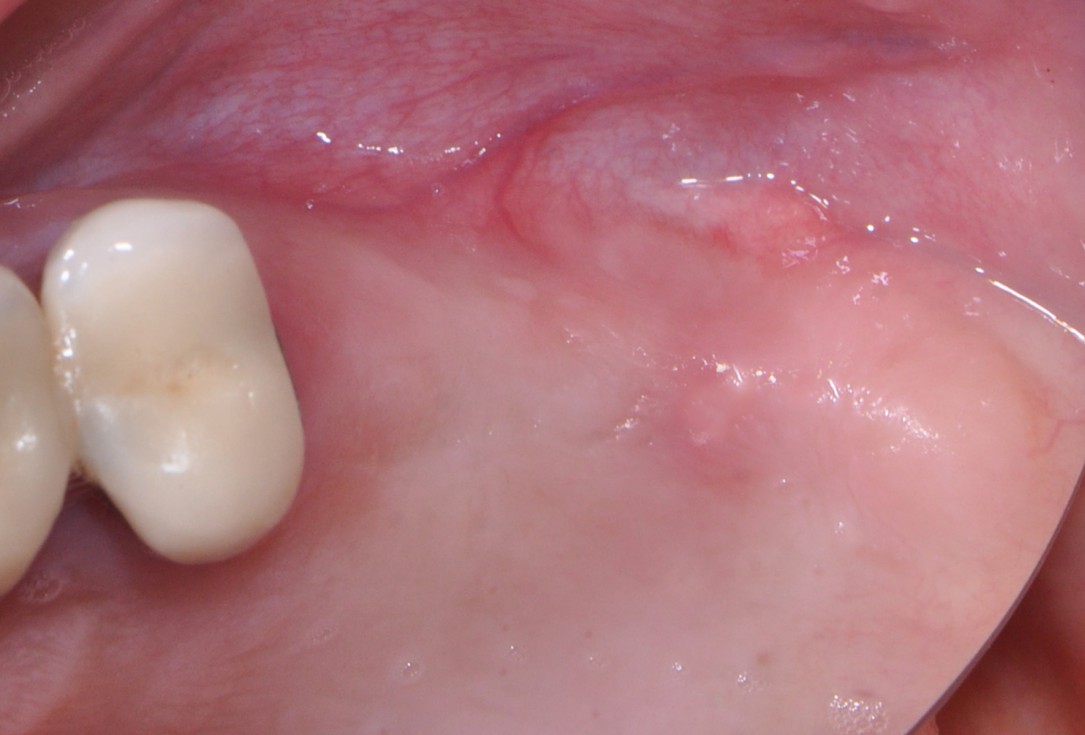

12/16 - Soft tissue regeneration

One-stage sinus lift - Dr. V. Kalenchuk